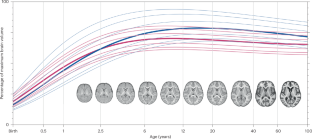

颅骨剥离人工智能模型利用来自大脑图谱的个性化先验知识,在不同年龄组、扫描仪和协议中产生一致的大脑提取。

A skull-stripping artificial intelligence model leveraging personalized prior knowledge from brain atlases generates consistent brain extraction across diverse age groups, scanners and protocols.